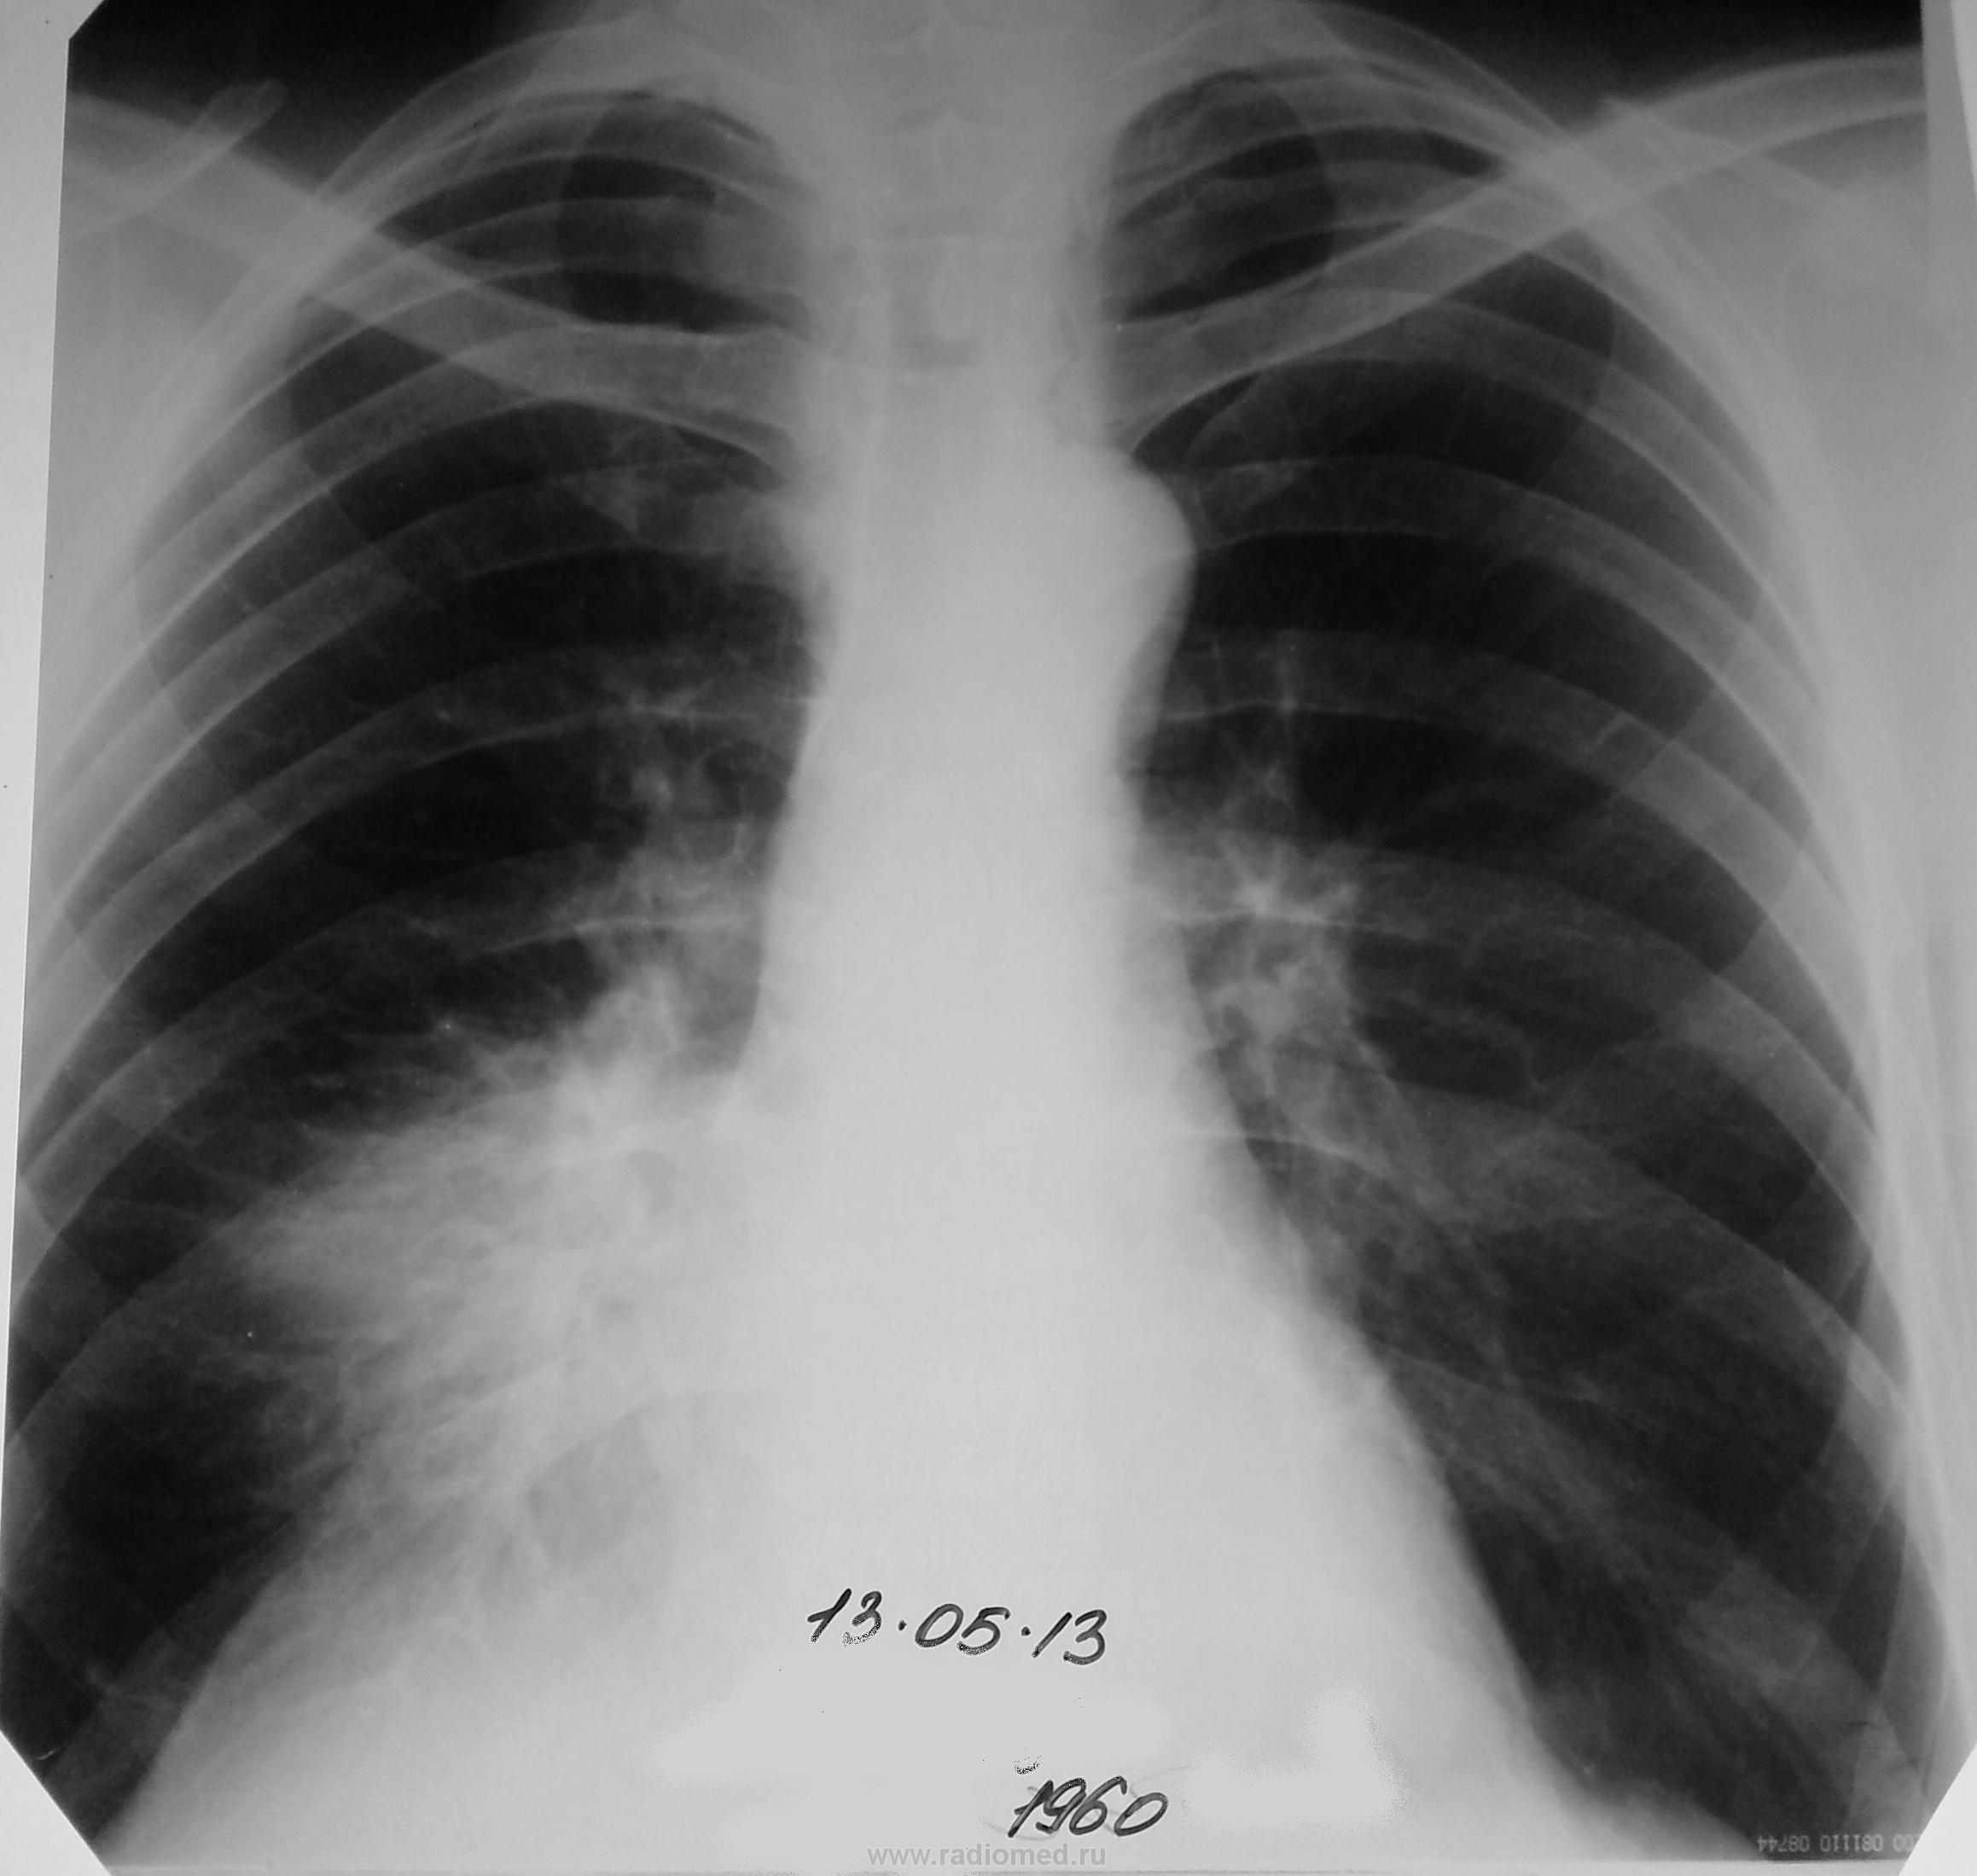

Лежит в терапии мужчина с правосторонней пневмонией шестой день.. сегодня явился на контроль.

рентген динамика на фоне лечения 5 дней почти нулевая. ( первый снимок был на флюорографе, предоставить не могу)

по теме - в заключении предположил ателектаз средней доли из-за центрального с-ч.  приятно видеть, что коллеги считают также.

Almo,  в анализах на пневмонию не тянет; лейкоциты в норме.  клинически - субфебрилитет, редкий сухой кашель. интоксикация минимальная.

Центральный рак.

А какие признаки центрального рака в данном случае? Пневмонии средней доли из-за анатомических особенностей могут часто иметь затяжное течение.

Могут, но в данном случае узлообразование очевидно, так что динамики улучшения мы не дождемся...увы.

Где узловое образование? Затемнение средней доли есть, уменьшение объема - сомнительно. Смущает немного более высокое стояние диафрагмы в переднем отделе.

Т.е. - вот ЭТО на узел "не дотягивает", вкупе со всеми остальными признаками?